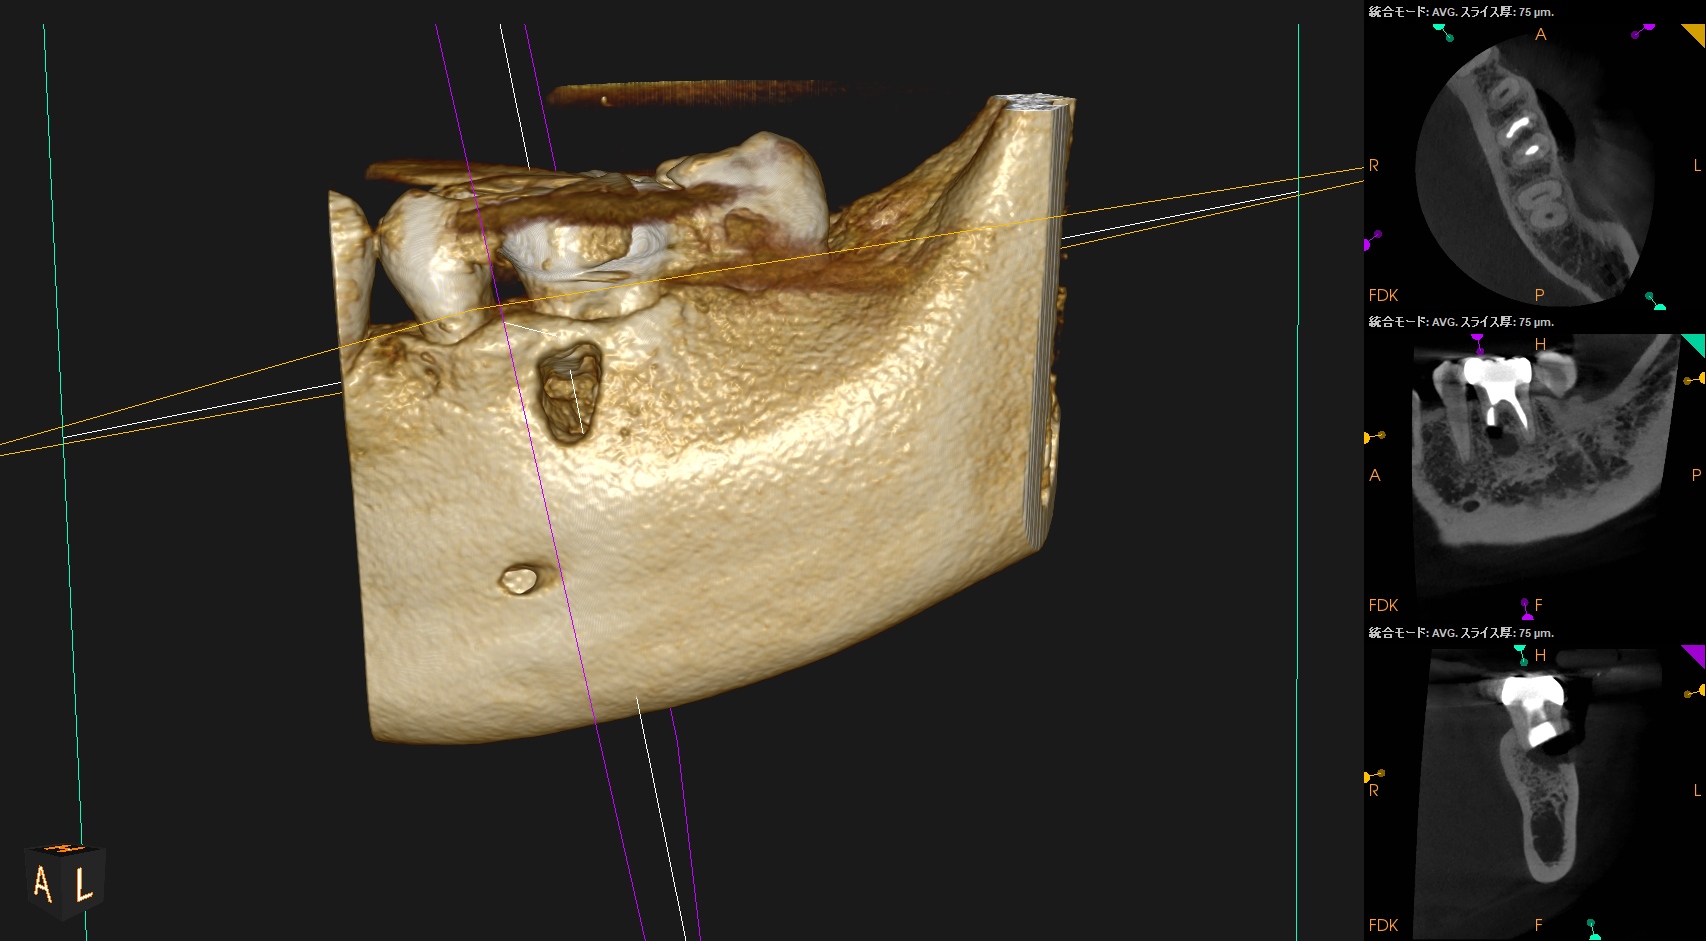

Post-op 1yr Endo test(2026.1.20)

術前の臨床症状は消失した。

外科の切開線の痕もない。

まさに完治だ。

術後の骨欠損は完治した。

ということで経過観察も終了である。